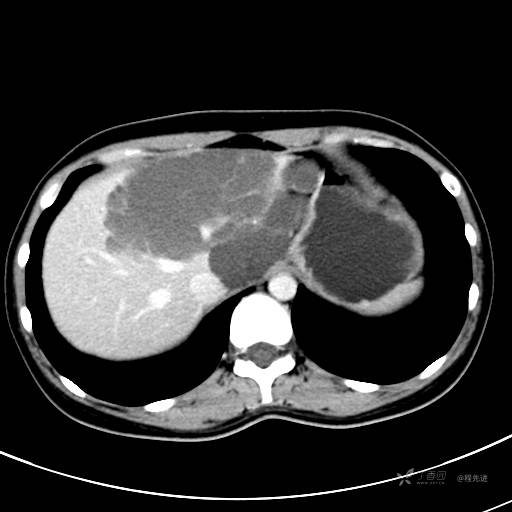

CT平扫+增强,每个序列3张图

CT值 平扫48HU 动脉期66HU 静脉期68HU 延迟期62HU